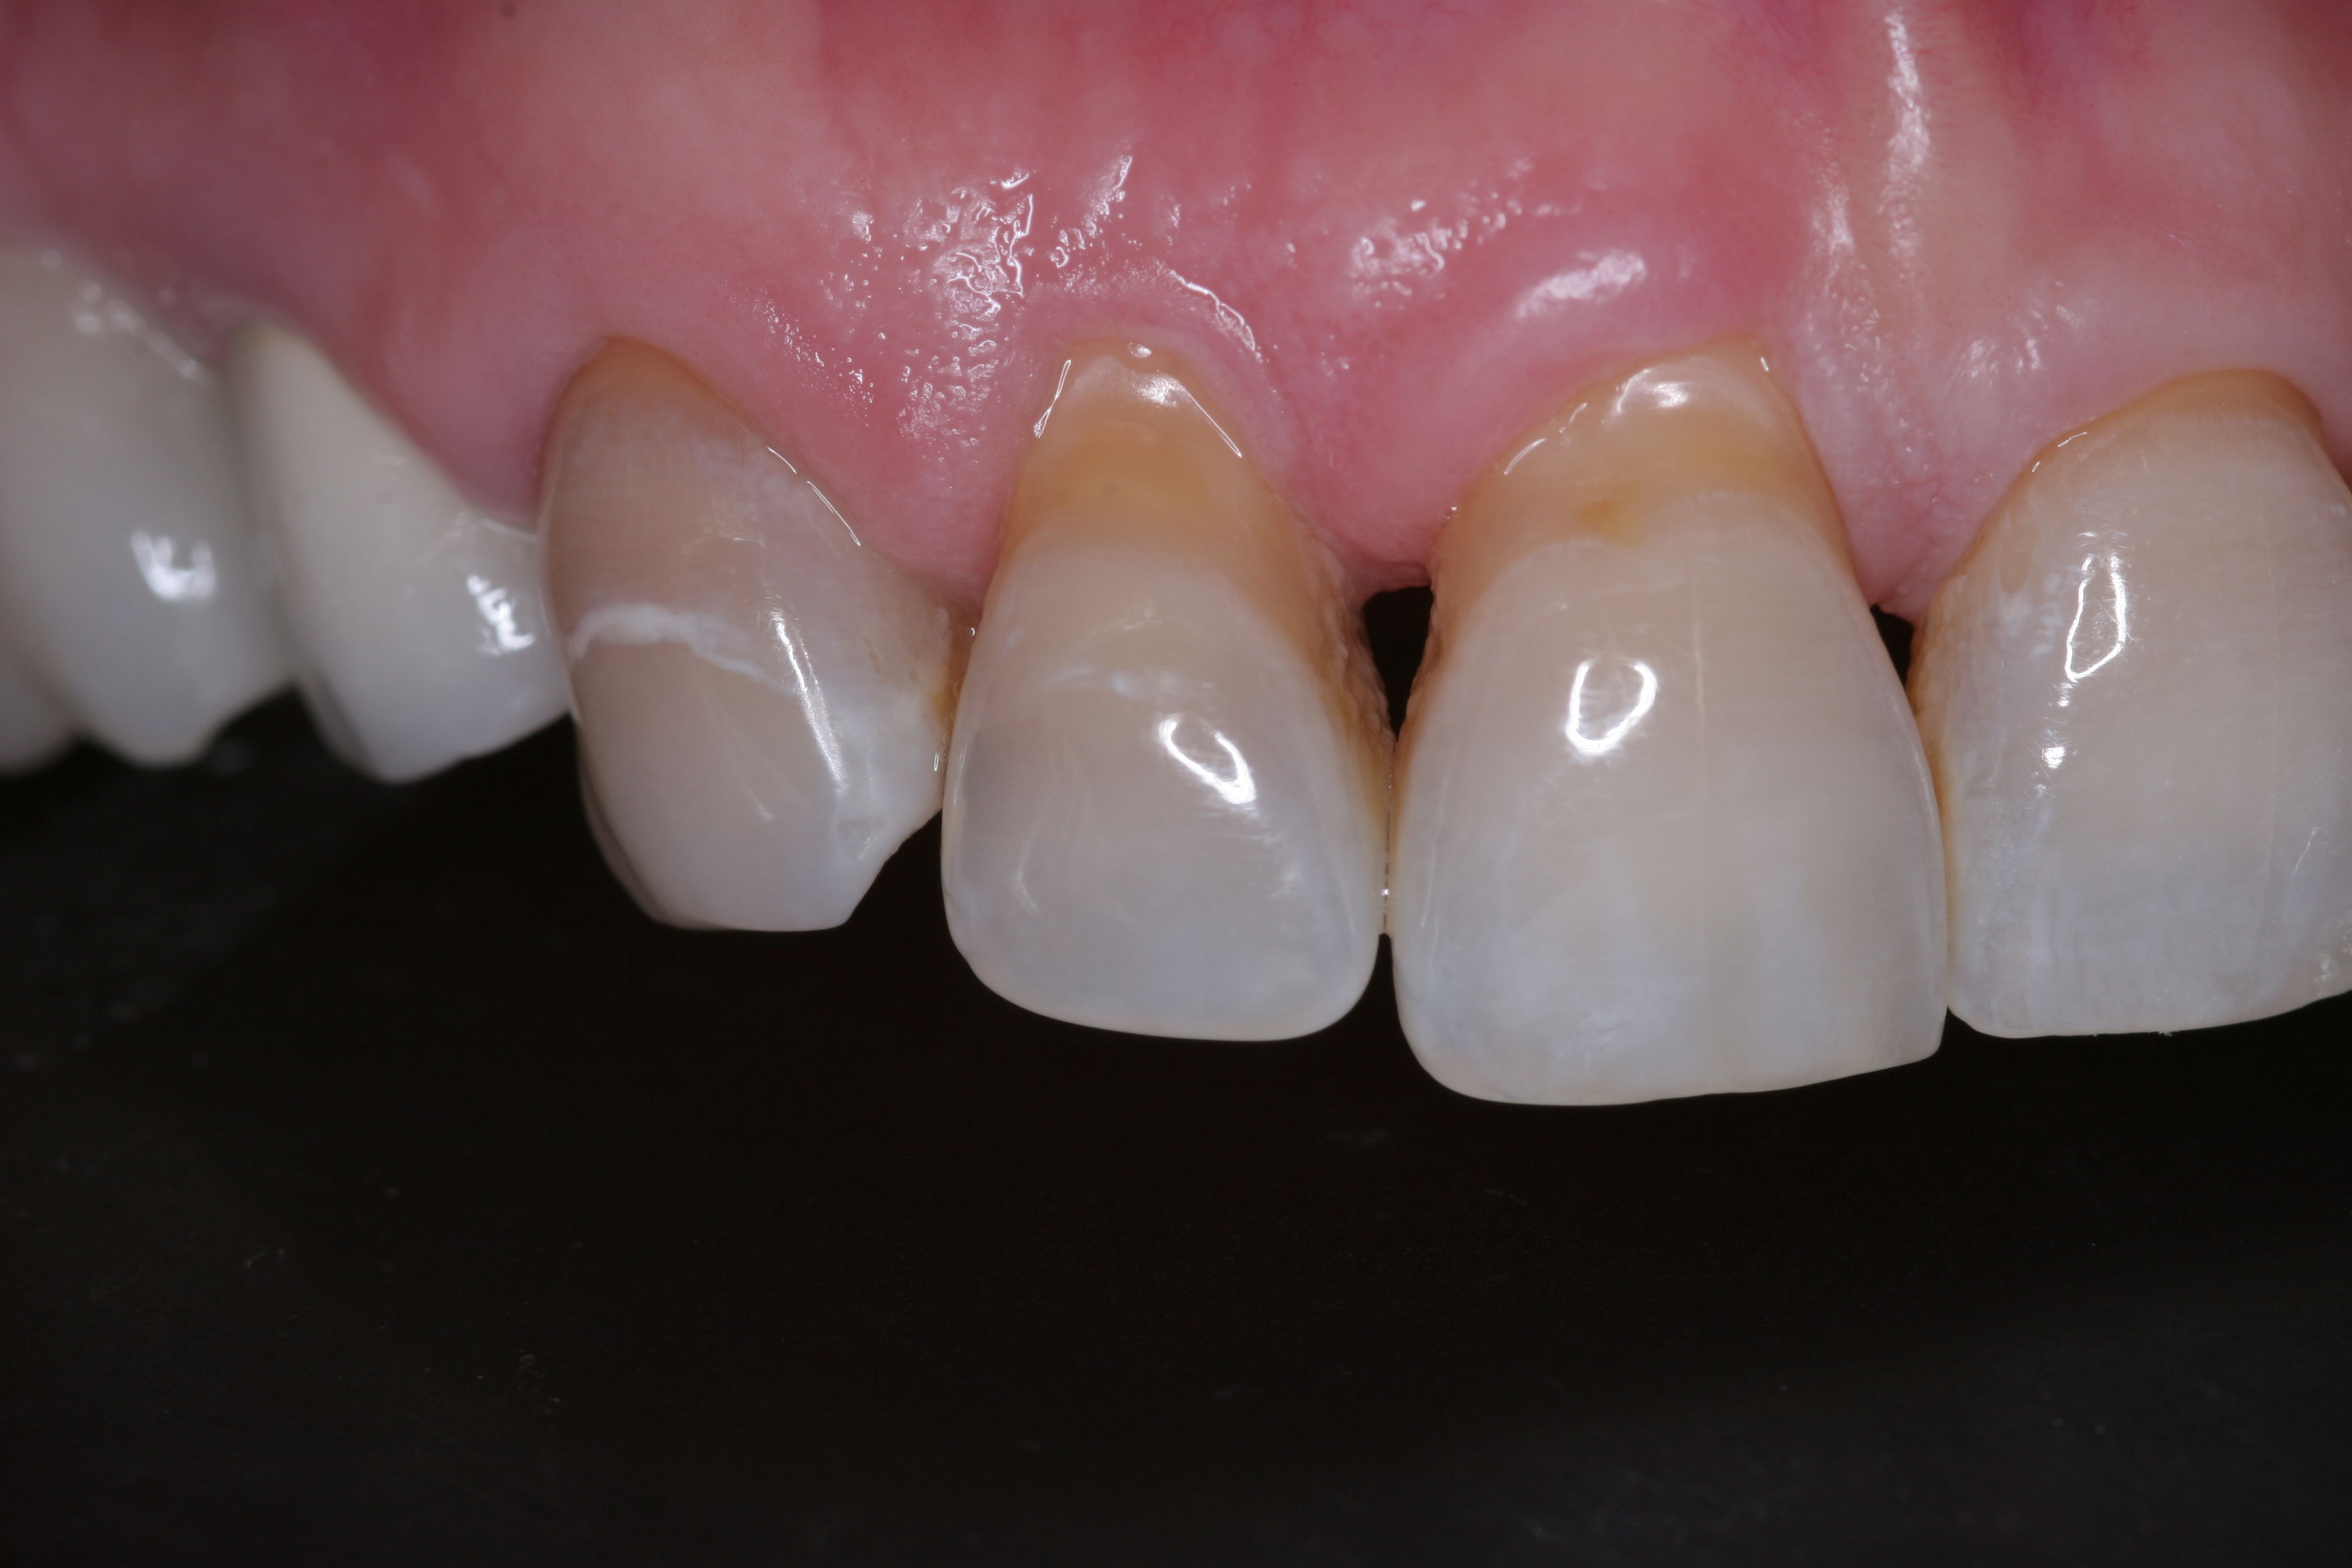

(11.) A patient presented with advanced generalized wear of her anterior teeth, and was displeased with their overall appearance because of their color and wear.

Figure 11

(12.) A patient presented with advanced generalized wear of her anterior teeth, and was displeased with their overall appearance because of their color and wear.

Figure 12

A patient presented with advanced generalized wear of her anterior teeth (Figure 10 and Figure 11). She was displeased with their overall appearance because of their color and wear (Figure 12). A complete examination was performed, revealing instability in her temporomandibular lateral poles bilaterally, sore muscles of mastication, advanced wear, a CR/MIP discrepancy, and loss of her anterior guidance due to the wear. Although the topic is beyond the scope of this article, the patient was also screened for possible sleep apnea. This included an evaluation of the Mallampati score, previous sleep therapy evaluation or treatment, snoring history, an evaluation of her neck size, her weight status, and the presence of the tonsils and their size. In every case, if this clinician suspects airway obstruction to be playing a role in tooth wear issues, the patient is referred to a sleep physician. The patient in this case displayed few apnea risk factors, and the patient’s anterior wear facets fit together like a “lock and key” pattern seen in parafunctional activity. Splint therapy was initiated to stabilize the joints and muscles. A repeatable CR position was verified through load testing. At this point diagnostic models, photographs, a CR bite record, and a facebow were taken and recorded.